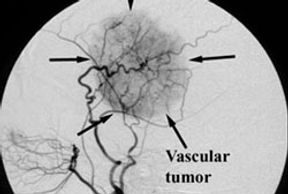

Embolization is done under X- ray guidance. A catheter is brought up through the femoral artery (artery in the groin) or the Radial (artery in the wrist) selectively into the blood vessel of interest that is feeding the tumor.

Pictures of the blood vessels are taken and if appropriate a glue type material is then injected into the feeding blood vessels to reduce the flow of blood to the tumor.